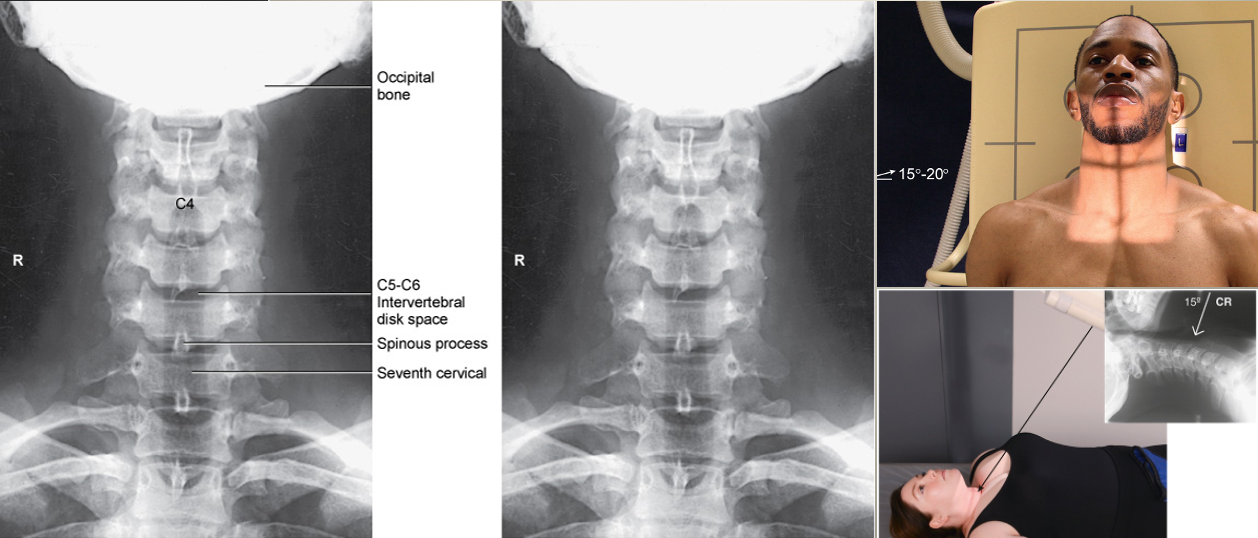

AP Axial C-Spine

• IR 10x12, 40 SID

• Pt supine or upright, arms by sides. Align MSP to CR and IR, TT or bucky. Adjust head so a line from lower margin of upper incisors to mastoid tips are perpendicular to IR. Ensure no rotation of head or thorax. Suspend on exhalation

• CR angle 15-20º cephalic to open up joint spaces due to superior vertebral body projecting inferiorly. CR enters C4 (Adams Apple). Collimate to ST margins

AP Axial Oblique C-Spine

• IR 10x12 portrait, 72 SID

• Pt erect, arms by side. Align MSP to CR, TT, IR, Bucky. Rotate patient 45º (may rotate head more to prevent superimposition of the mandible and upper vertebrae). Elevate chin to prevent mandible from superimposition of vertebrae, (AML) parallel with floor. Suspend respiration

• CR: RPO & LPO directed 15-20º cephalic to C4

Collimate to 4 sides of anatomy- soft tissue margins